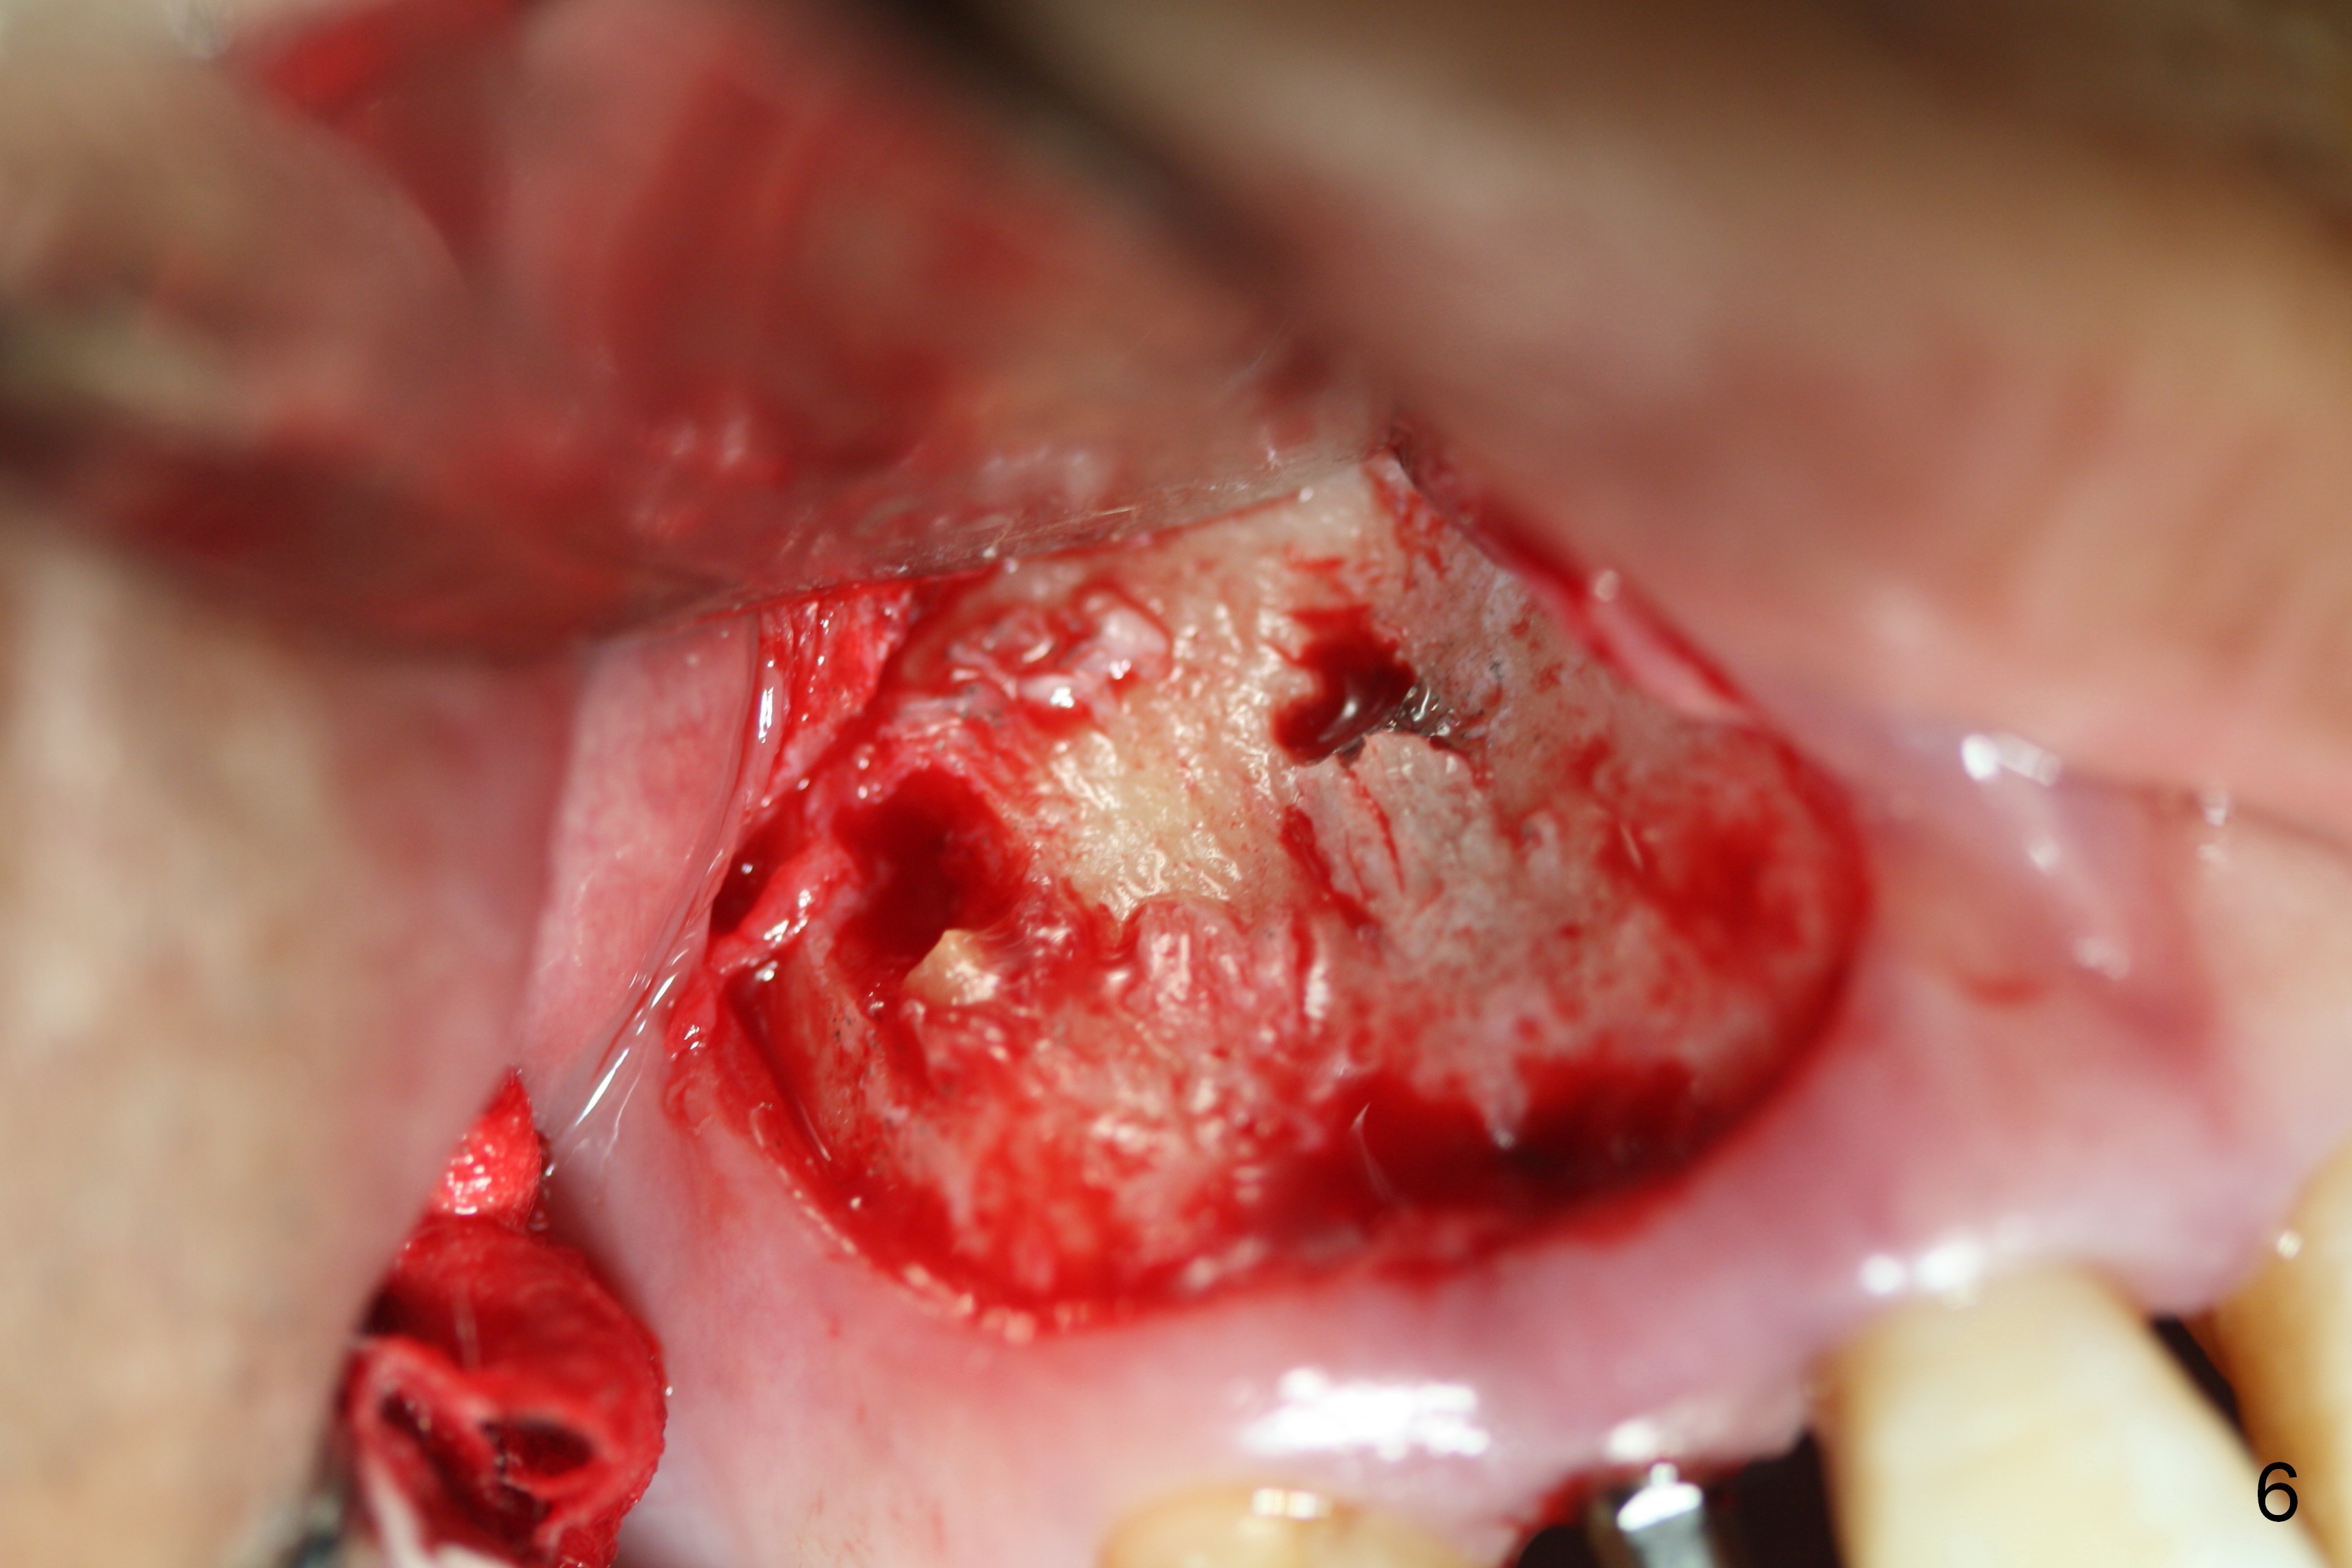

Preop exam shows the apparent wide ridge at #7 (Fig.1). What is ignored preop is the concavity in the apical buccal region (Fig.2 *). When a 3x16(4) mm 1-piece implant is being placed (Fig.3 *, flapless), the apical buccal plate vibration is felt. The biggest mistake is that initial osteotomy is ~ 6 mm shy of the implant length, partially because of 6 mm gingival height. Since the tooth #6 is symptomatic after RCT with paste overfill (Fig.4 >), apicoectomy is contemplated at #6 with exploration of the buccal plate at #7 (Fig.5). Since the implant appears to be long enough, implant apical resection is performed (Fig.6). Since there is coronal thread exposure due to previous periodontitis (Fig.7 <), bone graft is placed in these 3 defective areas after decortication.

Extending the initial osteotomy to the full length of the implant is critical. If perforation is detected early, the trajectory can be changed. Incision should be made if there is no CBCT study. The incision heals 1 and 4 weeks postop (Fig.8,9). The patient returns for final restoration 6 months postop. Apical defects appear to have healed at #6 and 7 (Fig.10,11). Fig.12 is taken 11 months postop and 5 months post cementation. The patient has an accident 9 months post cementation. In fact the implant is alright, while the tooth #6 fractures and #8 subluxates.